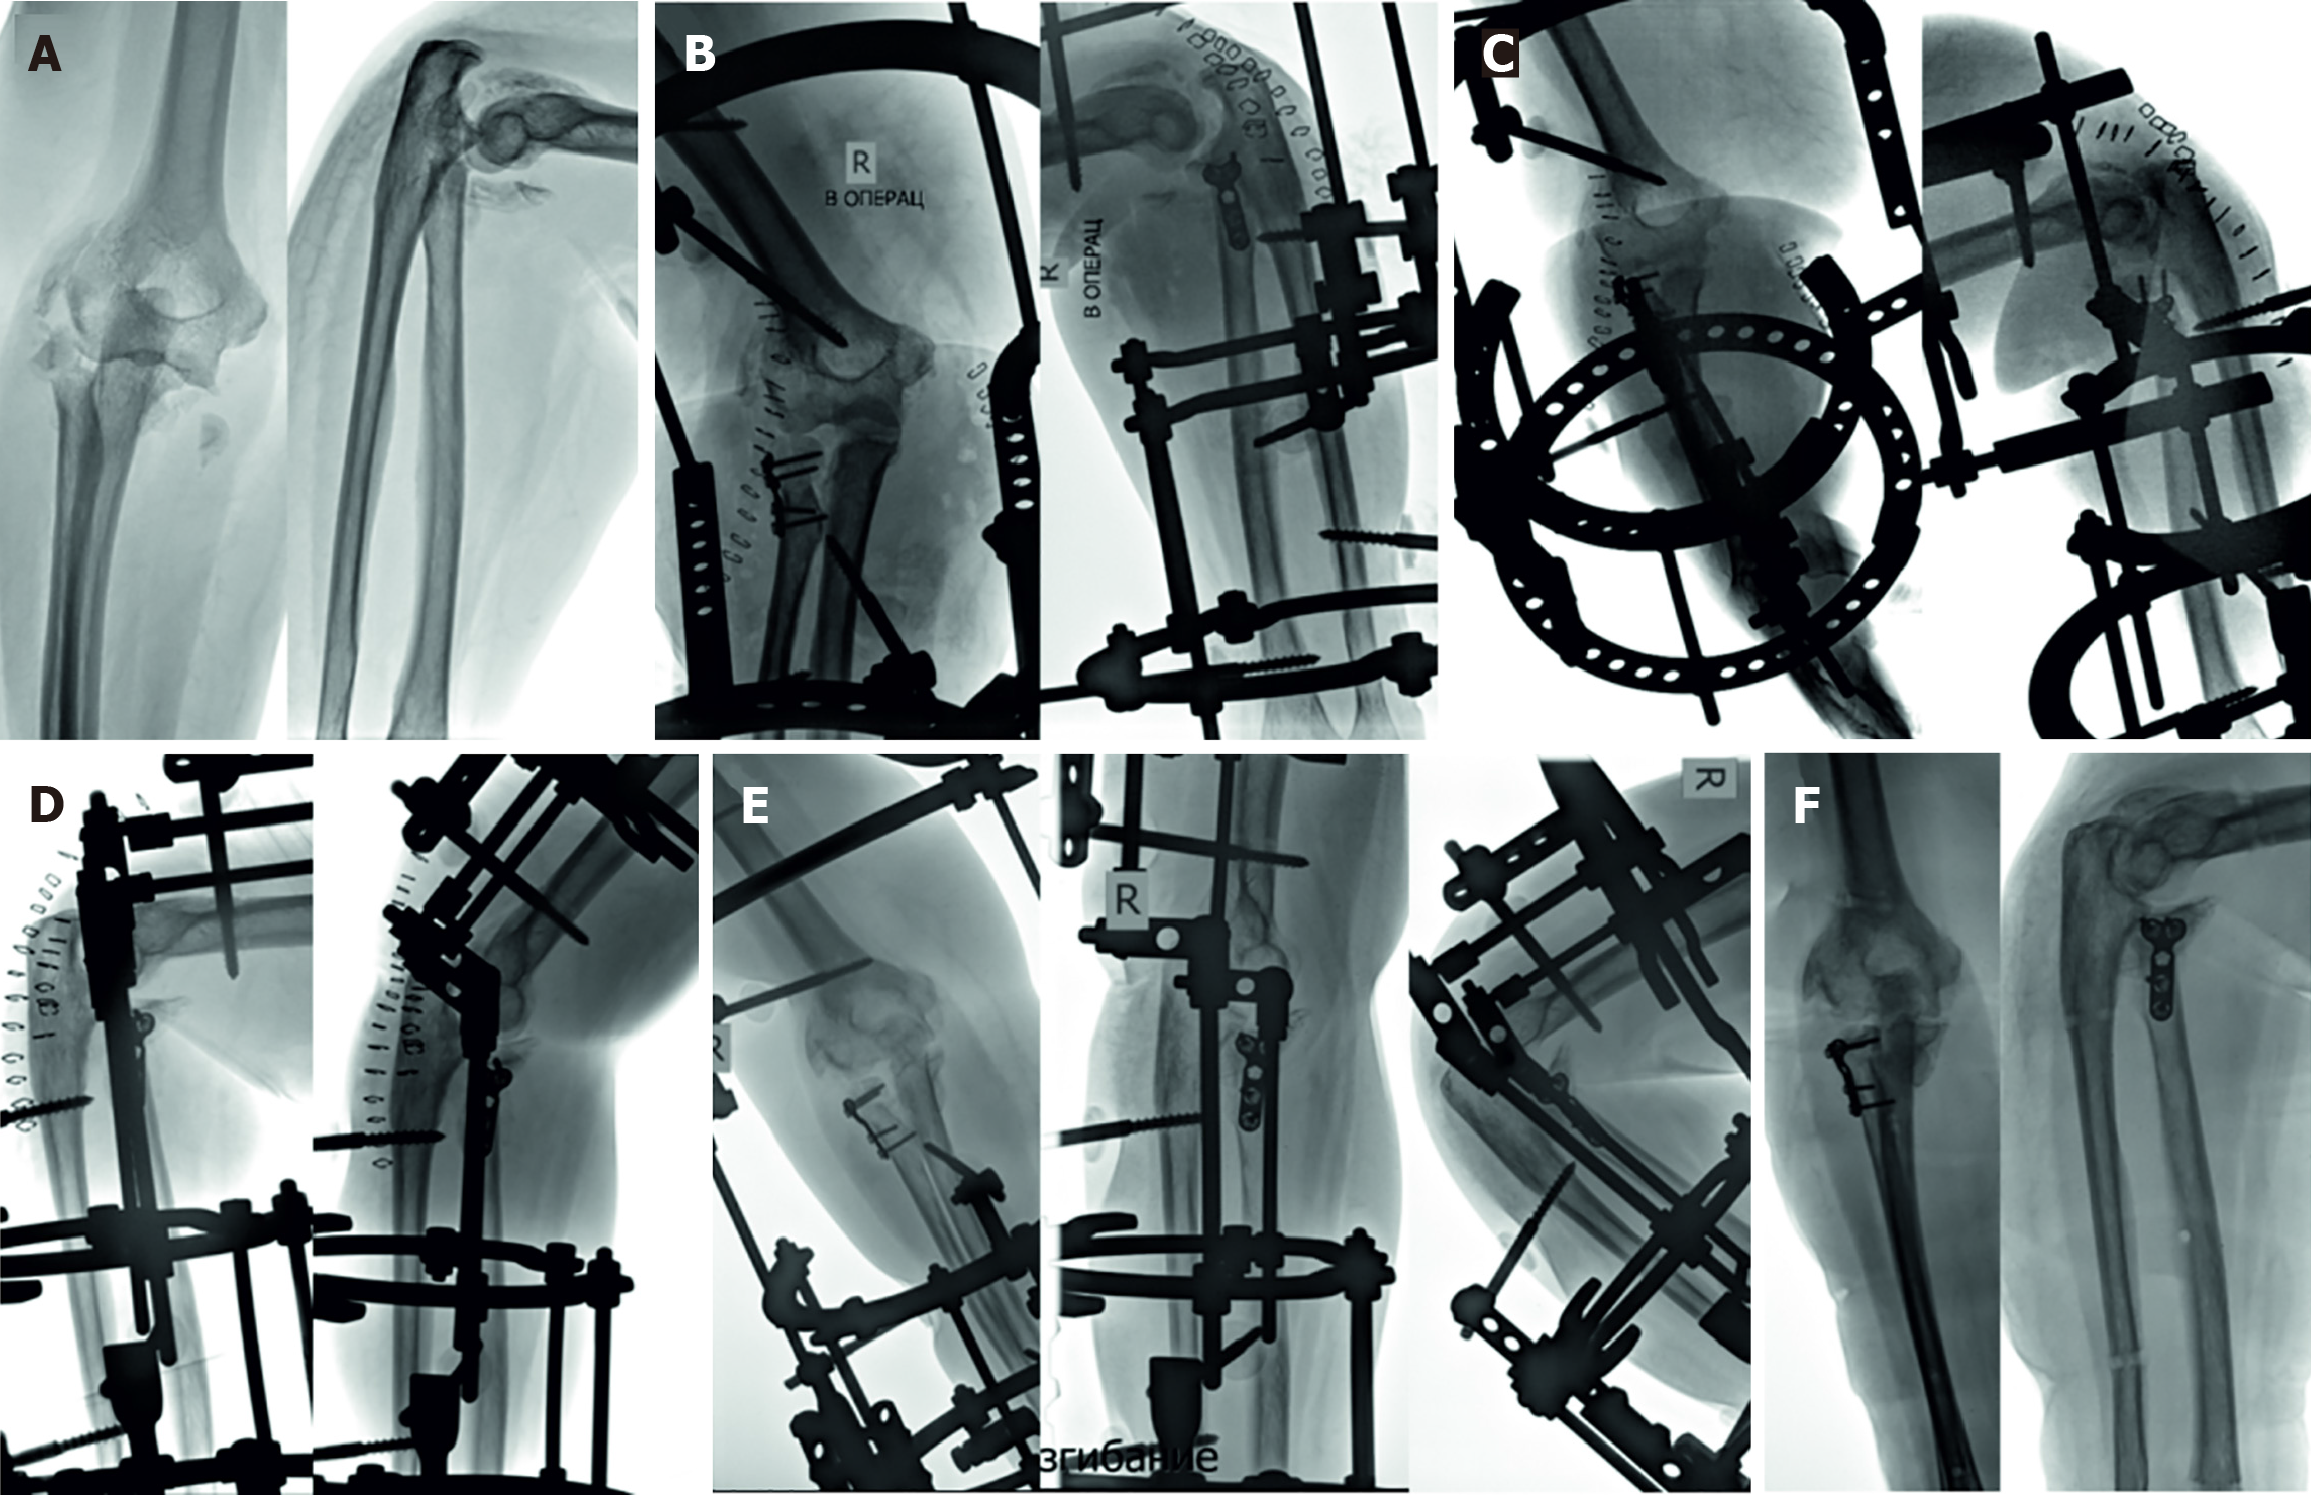

Figure 1

Figure 4 Customized external fixation with the Ilizarov frame combined with open reduction and internal fixation after failed closed reduction and cast immobilization of the forearm injury for 1.

5 months in a 66-year-old patient. A: Terrible triad: Mal-alignment of the right forearm with posterolateral dislocation, radial head nonunion, coronoid process malunion, heterotopic ossification; B: Open reduction and internal fixation of the radial head and fixation of the elbow joint with the Ilizarov fixator; C: Gradual reduction of the forearm bones for 8 days; D: Placement of hinges in the axis of the elbow joint upon completion of reduction for active range of motion (ROM); E: Due to obvious ROM limitation, a distraction rod system was attached on the anterior part of the Ilizarov fixator and active ROM continued for 12 days to restore the function of the elbow joint; F: Outcome at 2 months after surgery upon removal of the Ilizarov fixator, bone union and functional recovery.